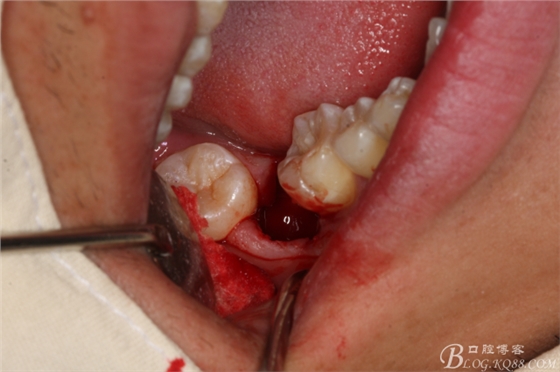

圖25.同樣的方法拔除37.

圖26.拔除34

圖27拔除的34、37、44、47.